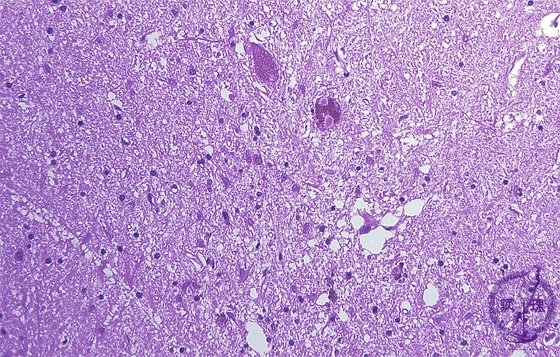

Microscopic findings (H.E. middle magnification): Melanin-containing neurons of substantia nigra were decreased in number and remaining neurons contained Lewy bodies in their cytoplasm (arrow). Melanin pigmentation identified in the substance of the areas in which neurons disappeared.